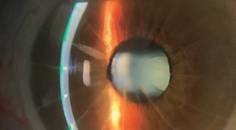

Treating Ocular Surface Disease With Scleral Lenses